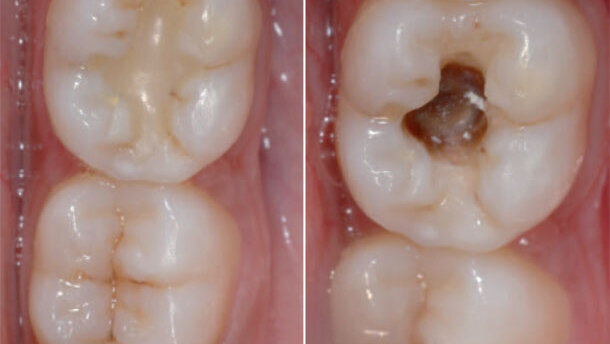

A 21-year-old male patient presented complaining of sensitivity and mild pain when chewing on tooth #36. During examination, an under filled tooth with poor marginal seal and marginal discoloration was visible. The peri-apical radiograph indicated secondary caries.

After careful removal of the faulty composite restoration, the cavity was treated with the fluoride-releasing bonding system Fl-Bond II and restored with Beautifil Flow as a base and Beautifil fluoride-releasing materials (all SHOFU). Effect colours were used on the occlusal surface to mimic the adjacent tooth.

The main challenges in this case were the removal of the faulty composite restoration with minimal intervention of the healthy tooth structure and the mimicking of the occlusal anatomy and proper shade.